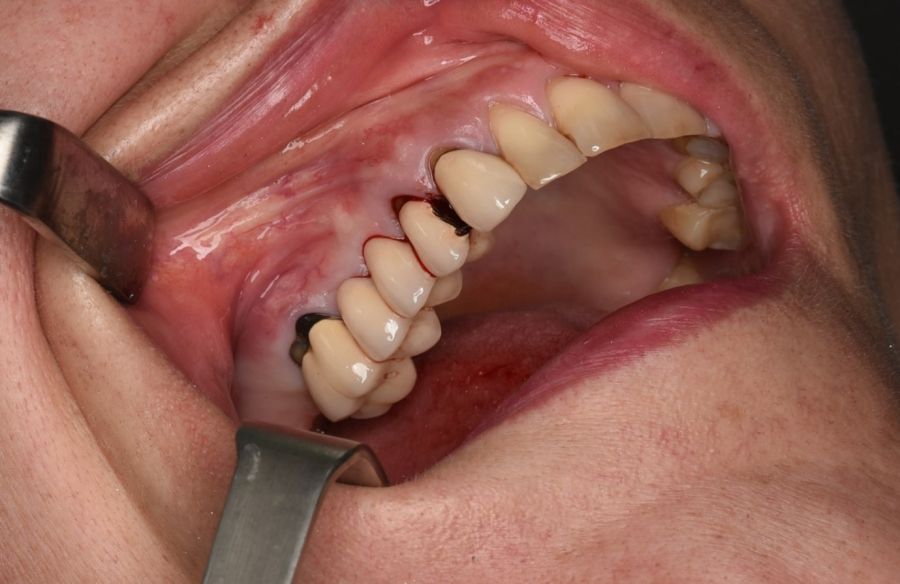

Se presenta el caso clínico de una paciente de 46 años que acudió remitida por su odontólogo habitual por movilidad y dolor en relación a prótesis fija dentosoportada en maxilar derecho, con pilares de prótesis en el canino superior derecho (1.3), primer premolar superior derecho (1.4) y segundo molar superior derecho (1.7).

En la historia clínica, no se evidenciaron antecedentes médico-quirúrgicos de interés, alergias medicamentosas conocidas, ni hábitos tóxicos y no presentaba tratamiento médico habitual. Se observó a la exploración intraoral la movilidad de la prótesis fija y caries bajo las coronas con afectación radicular de los pilares 1.4 y 1.7 (Figura 1).

La intervención se llevó a cabo bajo anestesia local mediante técnica infiltrativa con Articaina/Epinefrina 40 mg/ml + 10 microgramos/ml solución inyectable (Inibsa®, Lliçà del Vall, Barcelona, España), de los nervios alveolares superiores derechos posterior y medio, nervio infraorbitario derecho con la técnica intraoral y nervio palatino anterior a nivel del agujero palatino posterior. Se realizó la sección de la prótesis distal a la corona 1.3 con turbina y fresa de Lindemann, y se procedió a la exodoncia de los pilares de la prótesis 1.4 y 1.7, y el legrado minucioso de sus lechos alveolares y del granuloma apical de 1.4.